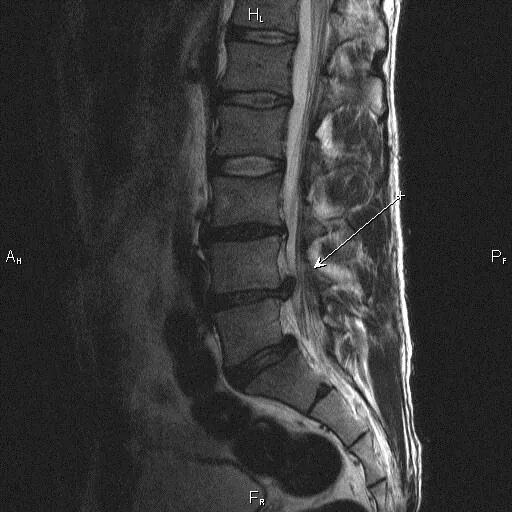

Грыжа диска мрт